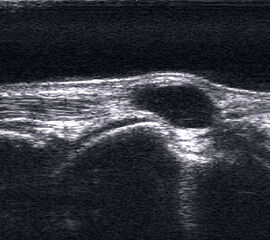

Echofreie Vorwölbung der Gelenkkapsel durch einen Gelenkerguss mit osteophytären Ausziehungen am Knorpel-Knochen-Übergang.

Abbildung 7

Lagerung: Rückenlage und ggf. Bauchlage.

Schnittebene: Ventraler (ggf. auch dorsaler) LS über dem OSG.

Referenzstrukturen: Distale Tibia und Talusrolle, teils verändert durch osteophytäre Randzacken mit Schallauslöschung und Pseudousuren. Auch die darüber liegende Gelenkkapsel kann von der normalen Anatomie erheblich abweichen.

Befunde: Echofreie Vorwölbung der Gelenkkapsel durch Erguss (Abb.7). Verbreiterter synovialer Randsaum, PD ggf. positiv. Bei ausgeprägter proliferativer Synovialitis mitunter fingerartige echogene Binnenstrukturen, bei Kompression Aquariumeffekt oder weitgehende Auffüllung der Gelenkapsel durch Proliferat. Bei aggressiver rheumatoider Arthritis breites echogenes, auf Knochen und Knorpel übergreifendes Pannusgewebe. Alle Anteile der Gelenkkapsel sind zu untersuchen. Daher auch Untersuchung in Bauchlage. Eine bakteriell bedingte Arthritis ist sonographisch nie sicher auszuschließen.